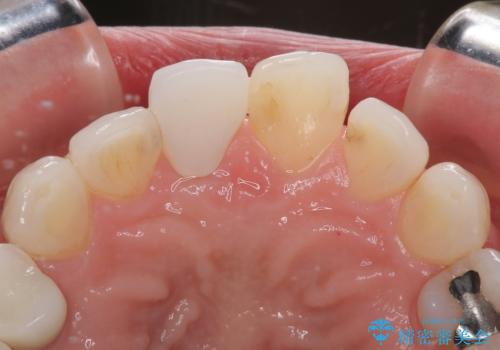

まずは根管治療を行い、痛みの消退を確認してからオールセラミッククラウンによる補綴治療を行うこととしました。

黄ばんできてしまった小臼歯部のクラウンは、根尖部に症状を認めないため、そのままオールセラミッククラウンによる補綴治療を行うこととしました。

初回の根管治療で痛みや違和感は消退したため、その後は速やかに補綴治療を行いました。